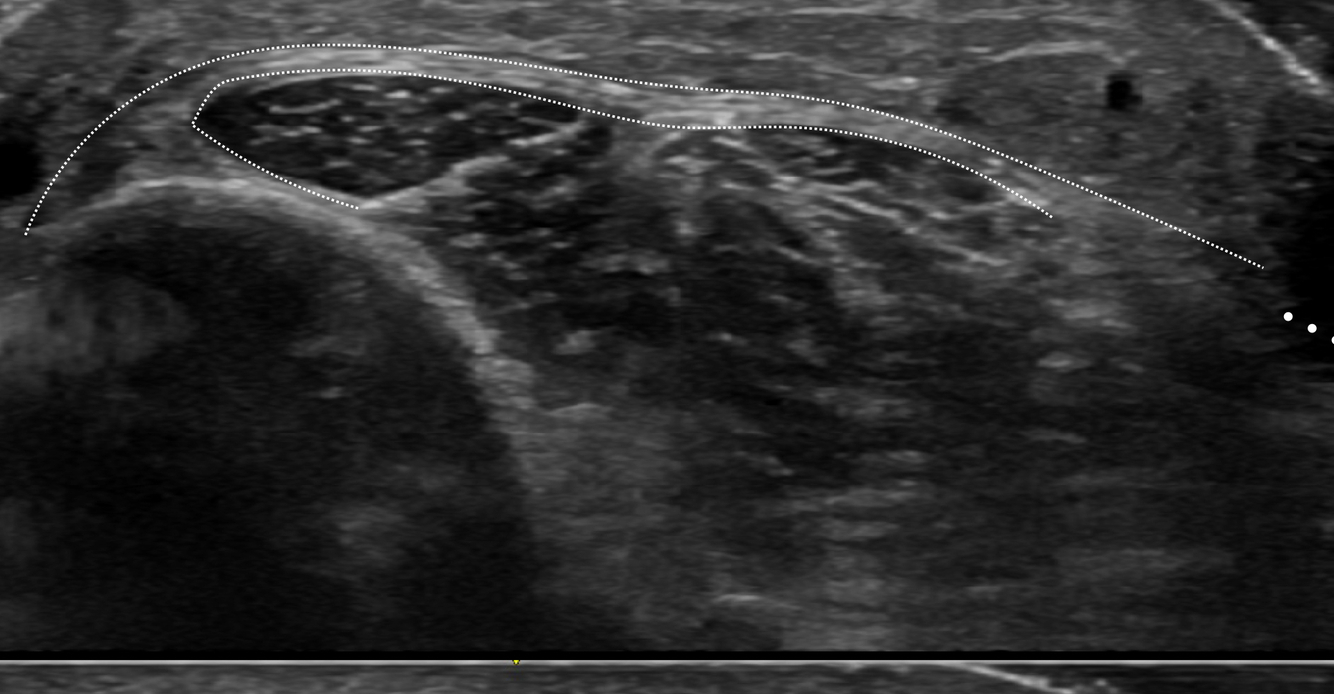

Identifier les structures suivantes

Kyste ganglionnaire intra-neural (où il y a des petites étoiles